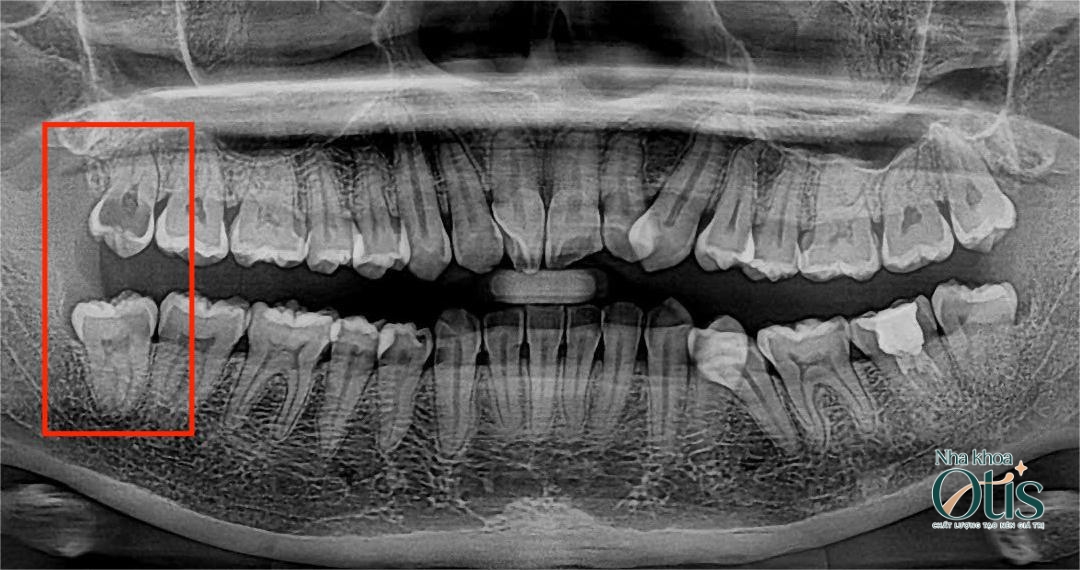

- Thăm khám kỹ lưỡng và chụp phim CT: Bước này giúp bác sĩ đánh giá chính xác tình trạng chân răng, xương hàm cũng như mối liên hệ với dây thần kinh. Đây là bước quan trọng giúp bác sĩ đưa ra phác đồ nhổ răng an toàn nhất.